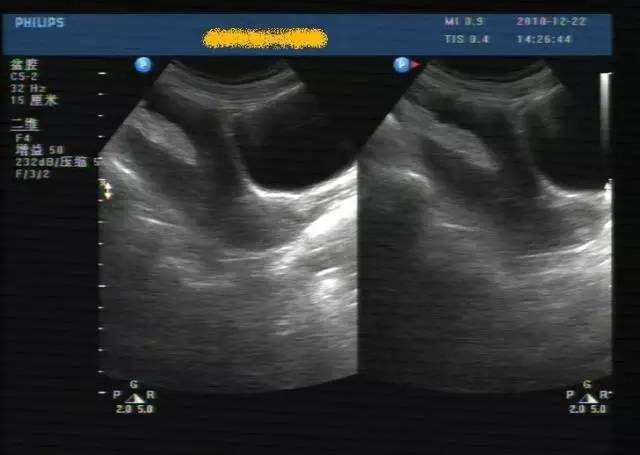

子宫穿孔的超声诊断

超声典型病例子宫穿孔

子宫穿孔彩超下表现

子宫穿孔彩超图

子宫穿孔b超图片